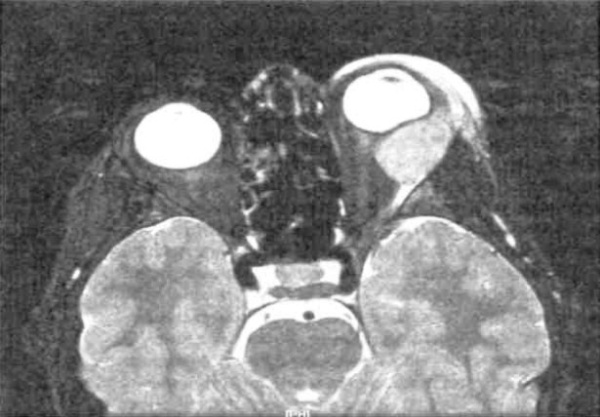

(Справа) При МРТ Т2 ВИ в аксиальной проекции регистрируется характерный низкий Т2 сигнал как внутриглазного, так и экстраокуляр-ного компонентов инфильтративного новообразования, что подтверждает диагноз меланомы глаза.